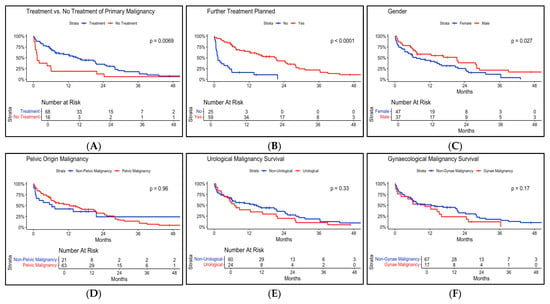

Background/Objectives: Malignant ureteric obstruction is an increasingly common problem; however, its treatment remains challenging due to associated poor survival and quality of life outcomes. There is a lack of consensus on how to best manage these patients. We provide a description of the survival outcomes, renal function outcomes, complications, and prognostic factors associated with the treatment of malignant ureteric obstruction in a cohort of patients at our tertiary Urology unit. Methods: A retrospective review of prospectively identified patients treated for malignant ureteric obstruction at our tertiary Urology unit was performed. Obstruction was relieved with either retrograde insertion of a ureteric stent or percutaneous nephrostomy between the 1st of January 2018, and 31st of December 2023. Renal function, complications, and survival data were recorded. Subgroup analysis and survival analysis were performed to determine prognostic factors. Results: Eighty-four patients underwent treatment for malignant ureteric obstruction with a median survival of 197 days (3–1549 days). A total of 51% percent of patients had a stent-related complication requiring hospitalisation, resulting in a total of 966 additional days in hospital. A total of 78% of patients had improved renal function at 12 months. Factors associated with worse survival included emergency treatment of malignant ureteric obstruction, having no further oncological treatment, receiving no oncological-specific treatment for malignancy, bilateral obstruction, female gender, and poor Primary site, Laterality, serum Creatinine level, and Treatment for primary site (PLaCT) prognosis group (p =< 0.01). Conclusions: Patients with malignant ureteric obstruction have a poor prognosis despite intervention. Treatment is often futile and associated with a significant burden of complications related to ureteric stents and percutaneous nephrostomies.

Figure 1